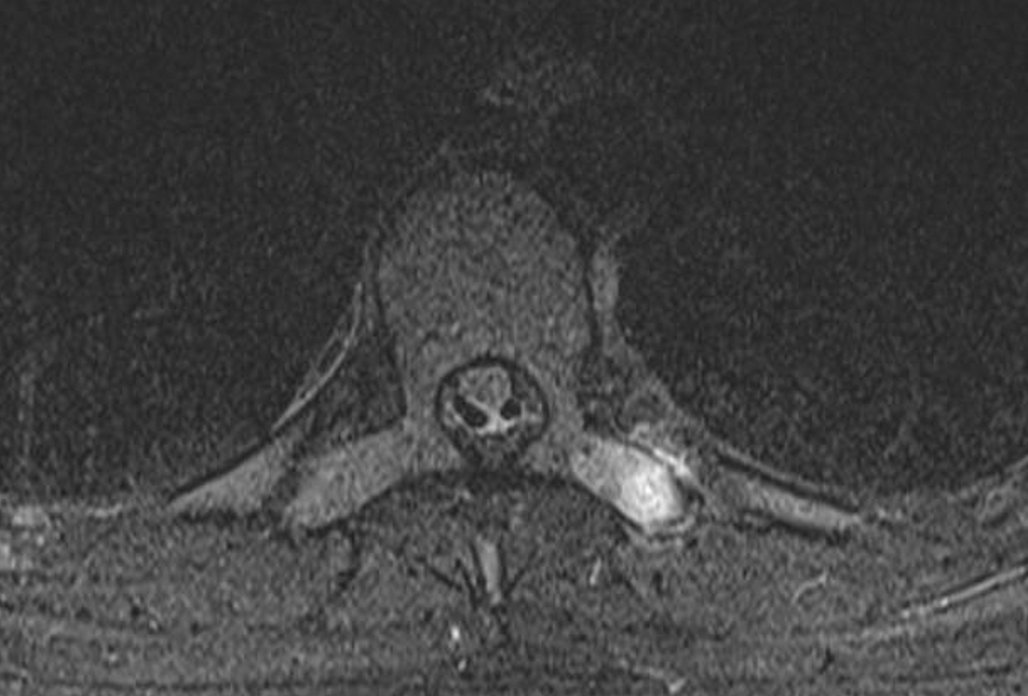

Similar case to yesterday's 🤩this time apophyseal injury at the level of the transverse process #spineimaging #medtwitter #radres #FOAMrad #radiology